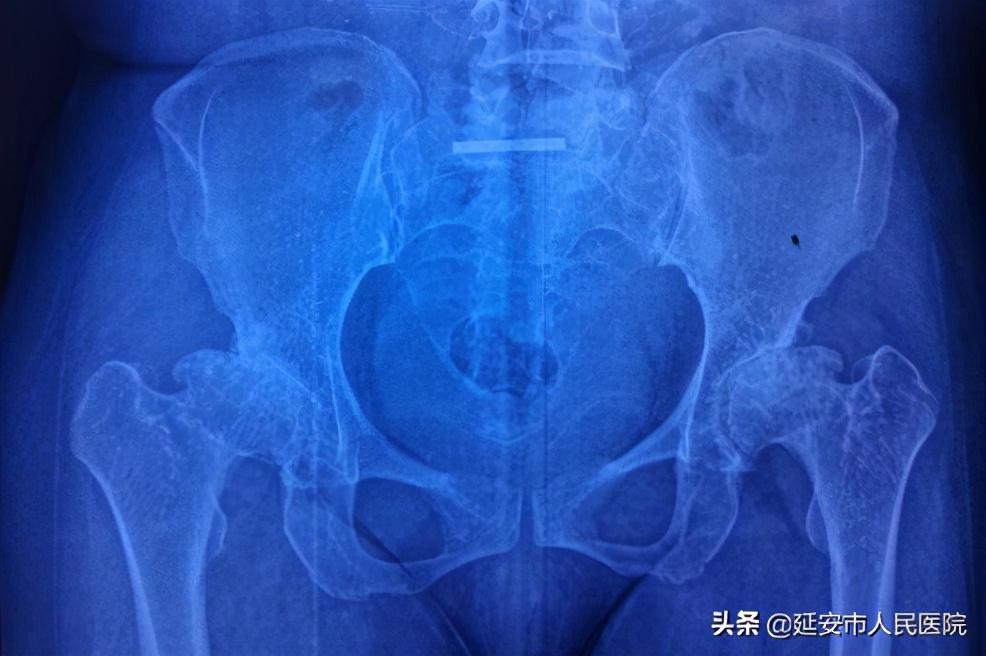

术前

46岁的患者郭女士,患有侏儒症,因先天性疾病,全身多关节畸形,约三年前出现双侧髋关节疼痛,逐渐加重,近日更是因疼痛严重影响日常生活。在当地医院就诊,诊断为双侧骨头坏死,须行双侧全髋关节置换术,但因为高昂的医疗费用,使患者及家属在诊治疾病的现实困难面前退缩了,美好的愿景往往不能战胜现实的困难,他们回去了。

可对于该患者而言,问题远不止手术费用和医疗技术,因患者身材矮小,身高只有1.36m,一般医疗器械公司没有如此小的假体可供患者选择、使用,没有器械及假体材料,手术只能暂时望而却步。